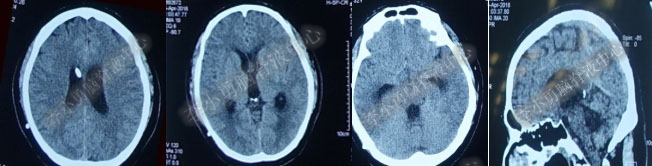

第1次内镜术后330余天即11个月(2017年4月),又开始出现头晕症状并逐渐加重。2017年6月13日(第1次内镜术后367天),行头部MRI(图-4)检查显示全脑室系统扩大。

图-4:2017年6月13日头部MRI

2017年6月19日(第1次内镜术后404天即一年零39天),因原症状加重,第2次住入该院。2017年6月20日(住院第2天),复查头部MRI(图-5)。

图-5:2017年6月20日头部MRI